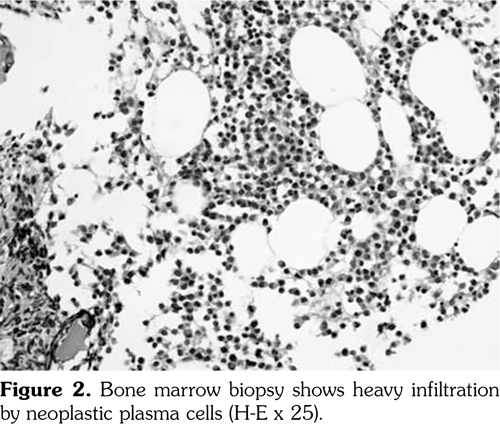

However, two years after the diagnosis of basal-cell carcinoma, the patient was re-admitted to the hospital due to complaints of feebleness, palpitation and cough lasting for 10 days. Laboratory analysis showed an increased white blood cell count of 20x109 L (NR 4-10x109/L), decreased red blood cell count of 1.28x1012/L (NR 3.5-5.0x1012/L), and platelet count of 45x109/L (NR 100-300x109/L). Serum electrophoresis revealed monoclonal protein of 68.24%. The urinary lambda (l) light chain was 0.186 (NR <0.05). Bone marrow biopsy revealed diffuse fibrosis with collagen deposition, heavy infiltration of neoplastic plasma cells (CD138, PC positive), and l light chain restriction (Figure 2-4) with a total ratio of 66% for original and naive plasma cells. Hence, the diagnosis of l plasmacytic leukemia was confirmed. However, our patient rejected to undergo further evaluation and treatment due to personal reasons.